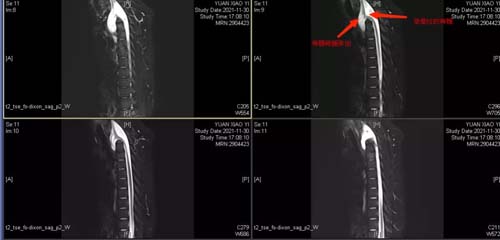

影像学资料:

颈胸段CT及3D融合:C6、C7、T1椎体骨质融合,C6、7呈“蝴蝶椎”样(半椎体并融合),椎体骨质变薄,T1椎体前缘不连续,椎管开放。

MR:符合C6-T1椎体发育不良并椎管闭合不全、脊髓脊膜膨出MRI表现。

术后MR,脊髓未受牵拉,脊髓脊膜膨出修补良好。